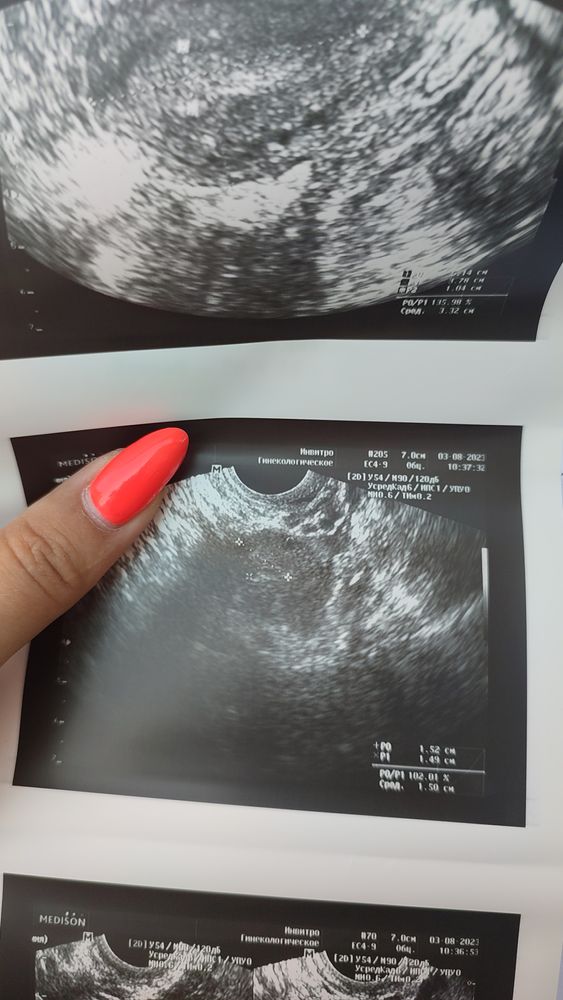

УЗИ и понятно что них не понятно

Это что за портянка?... 10 мм эндометрий- какая гипоплазия под вопросом :-/что за недостаточность фолликулярного аппарата? в общем этим узи можно только подтереться.

Узисты уже лекарства назначают? Что за треш, многовато на себя берет. Все нормально у вас, овуляция была, беременности нет, ничего критичного по УЗИ тоже нет.